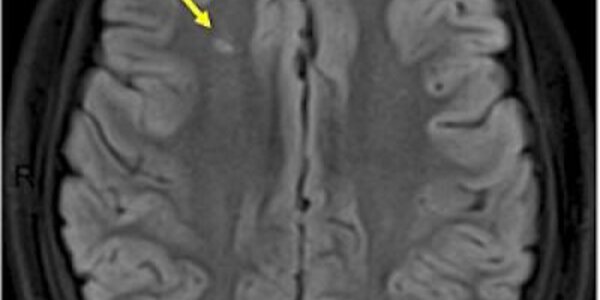

Monthly Transfusions Reduce Silent Strokes In Kids With Sickle Cell Anemia

Silent strokes are a loss of blood flow to parts of the brain. Such strokes do not cause immediate symptoms and typically go undiagnosed, but they cause damage. In kids, they can even lower IQ. Sickle cell anemia affects about 100,000 people in the United States and occurs most commonly in African-Americans. The disease, inherited from both parents, causes some of the patient's red blood cells, normally shaped like a saucer, to take on a crescent or sickle shape. These malformed cells are less effective at their primary job, conveying oxygen from the lungs to the rest of the body. The cells…